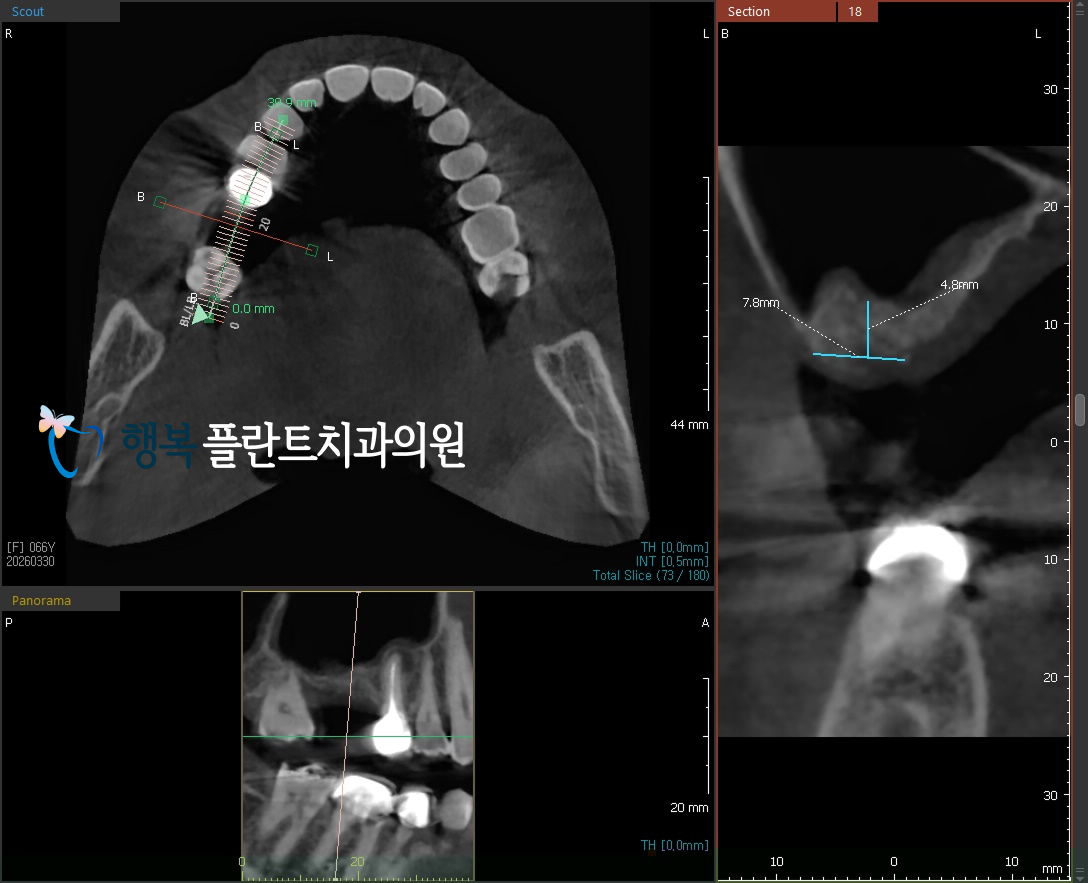

그렇게 3개월간 치유를 기다린 뒤 다시 CT를 확인해 보니 발치와 부위의 회복은 안정적으로 이루어지고 있었지만

상악동의 영향으로 인해 임플란트를 식립하기에는 여전히 수직적인 골 높이가 다소 부족한 상태였습니다.

이럴 때 무리하게 식립을 진행하기보다는,

필요한 만큼 상악동을 안전하게 들어 올려 뼈이식을 동반해야 하는데 이것이 바로 상악동 거상술입니다.

특히 이번 증례에서는 수압 거상을 활용한 상악동 거상술을 계획했습니다.

[임플란트를 심기에는 여전히 부족한 뼈]